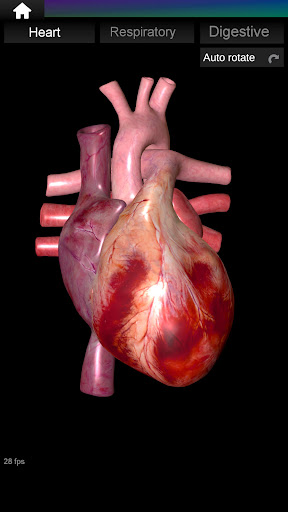

* Jantung, yang meliputi atrium, ventrikel, aorta, dan animasi organ ini.